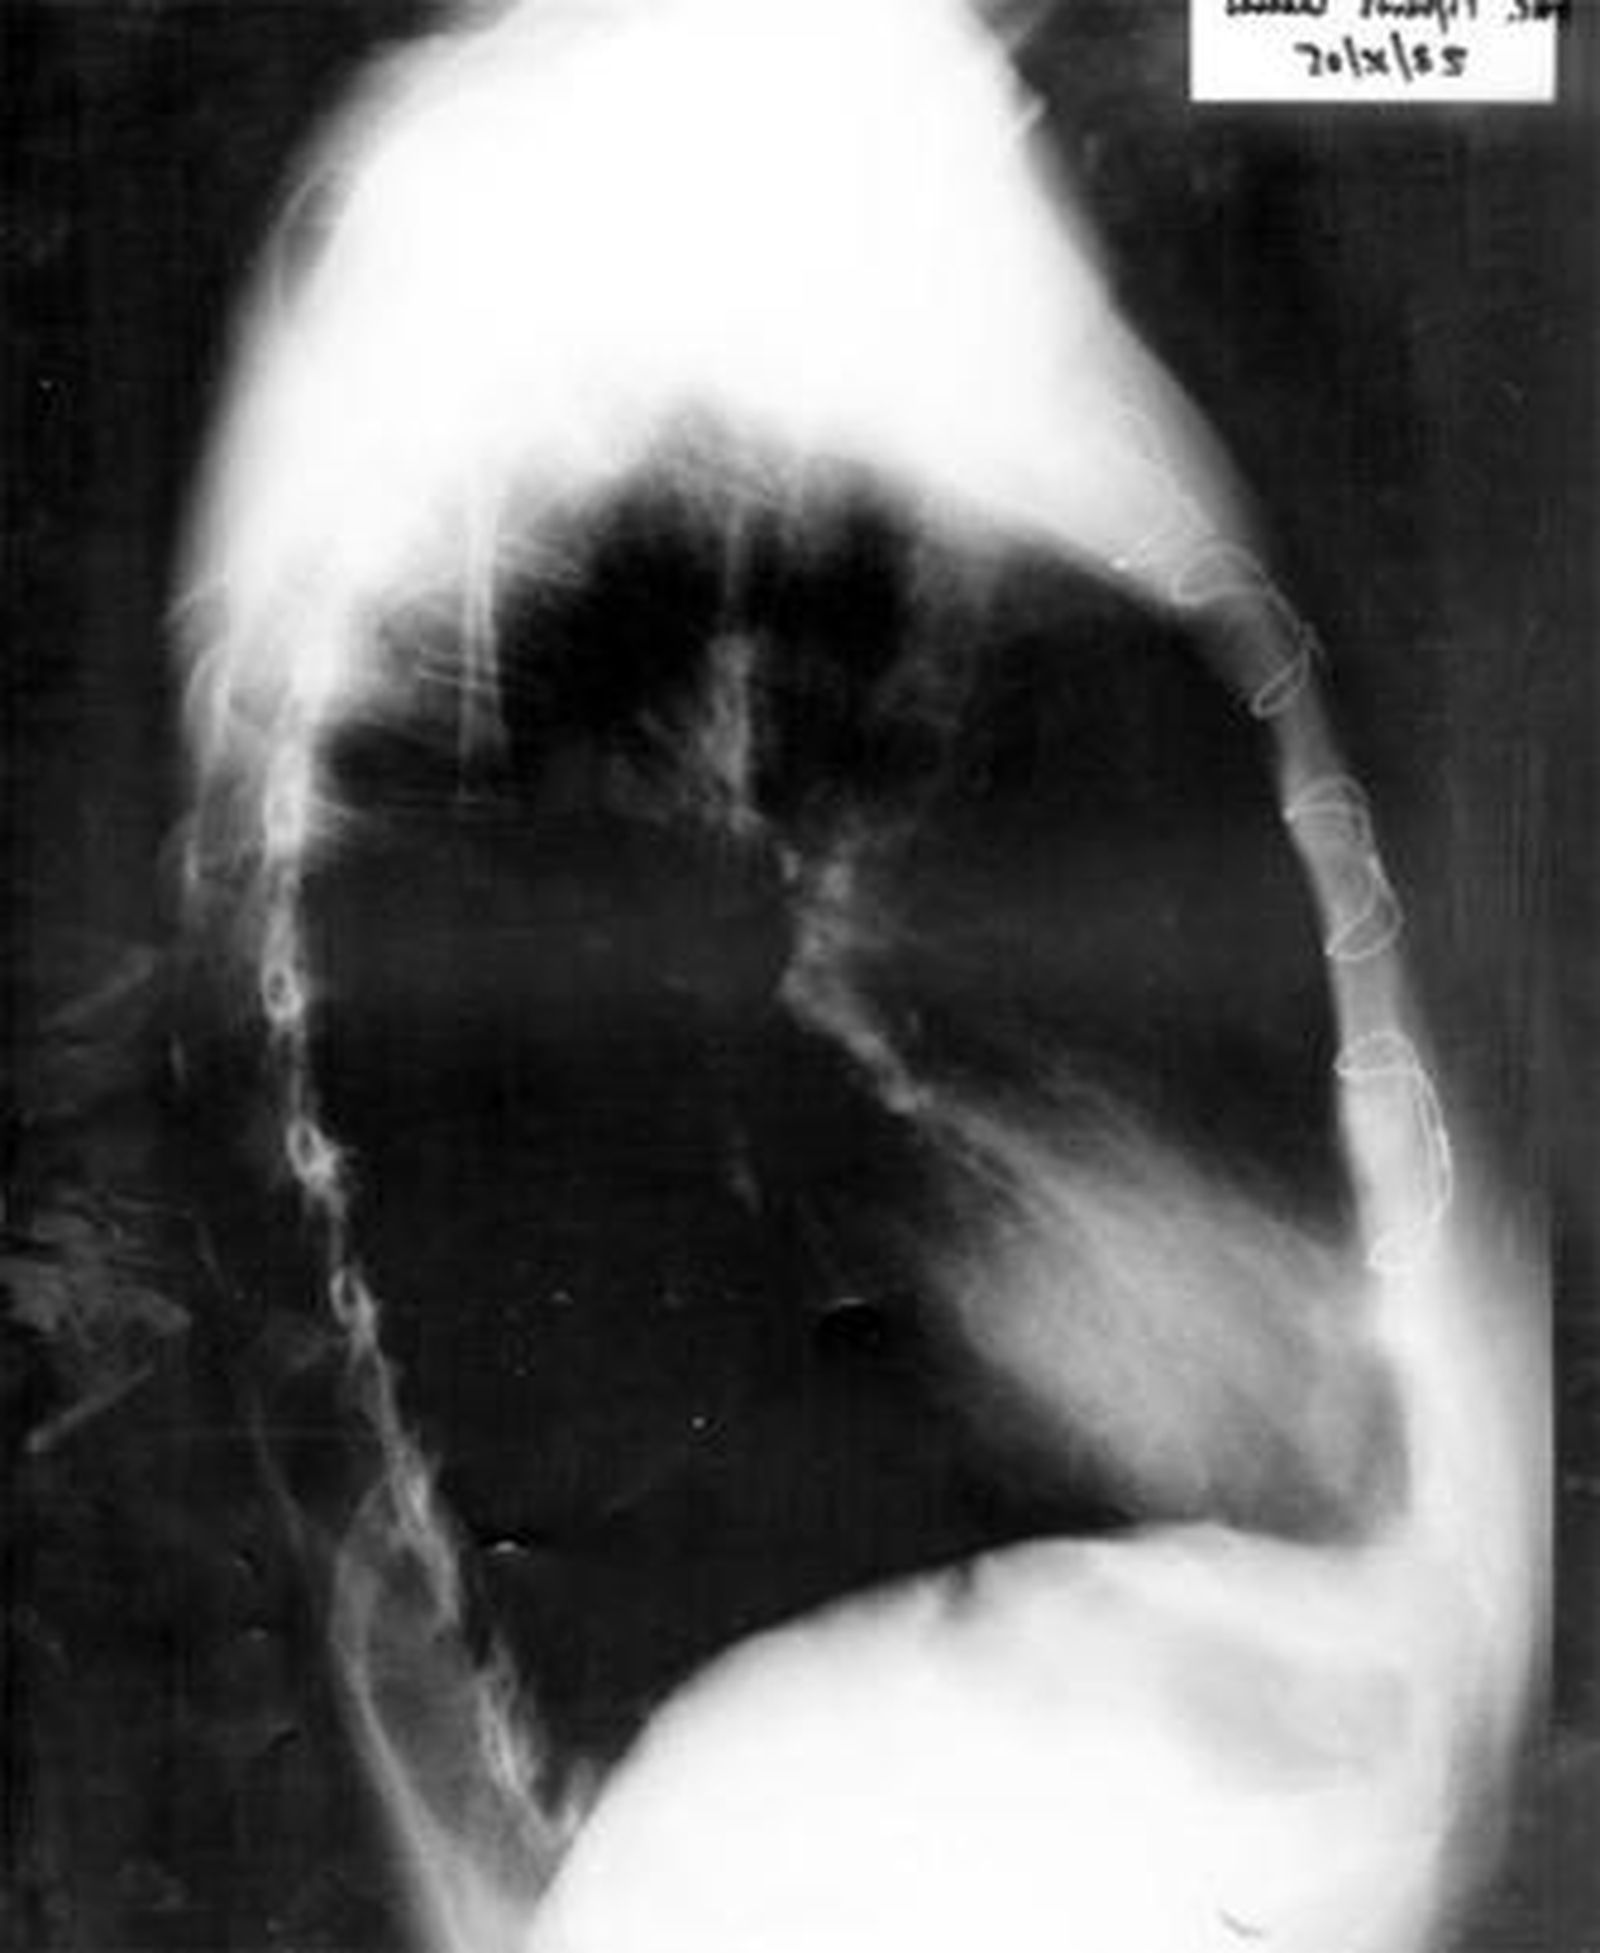

1. Imagen de las pruebas radiológicas realizadas a la paciente en las que se observa (en la ampliación) el cuerpo curvilíneo que resultó ser una aguja de sutura olvidada por el personal médico que le practicó la operación, en la que se intentó reparar el mal funcionamiento de la válvula mitral. Según los expertos, los objetos extraños son englobados por el organismo pero no se descarta que se mueva y tenga consecuencias.

Tras una primera revisión en abril de 2004, en la que no se vio nada raro, la paciente, aún con dolores y malestar, acudió en mayo a Urgencias del Hospital de la Axarquía -en Málaga-, donde, con dolor torácico punzante, le realizan pruebas radiológicas en las que se "evidencia imagen curvilínea de densidad metálica en localización de aurículo derecha". La aguja de sutura.